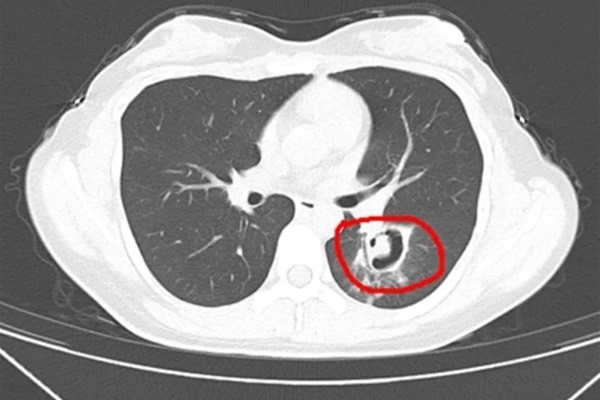

Sau một loạt kiểm tra, bác sĩ kết quả chụp CT phổi cho thấy những "chồi cây nhỏ" đã mọc ra từ phổi của cô Vương và họ nghi ngờ cô bị viêm phổi do nấm. Tiếp theo, bác sĩ tiến hành nội soi phế quản, phát hiện một lượng lớn mảng trắng trên thành đường thở. Sau khi xét nghiệm, xác định đó là Aspergillus.

Cô Vương được chẩn đoán mắc bệnh viêm phổi do nấm